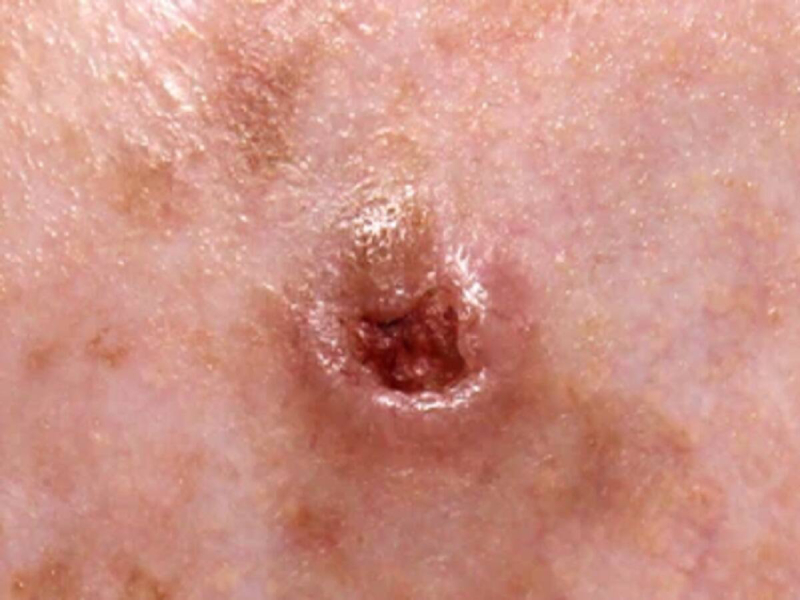

Tumors & Cancers

Discover symptoms & explore medicines and treatment options. Also read expert health articles about symptoms, the latest research, medicines and alternative treatments for every disease and medical condition.